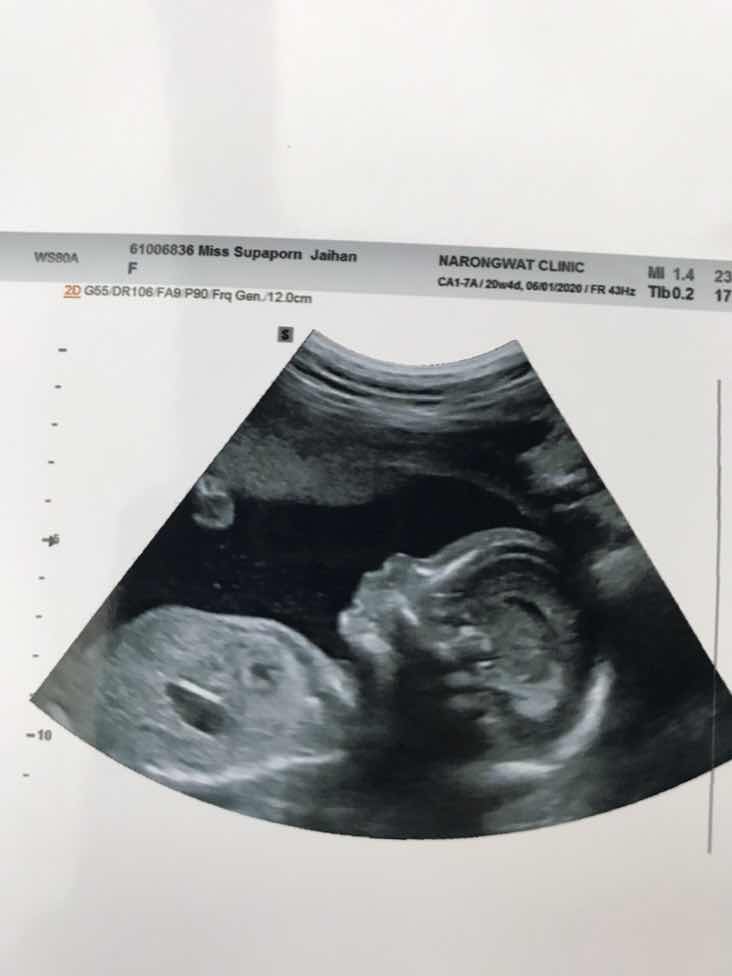

5 เดือนค่ะ 😍😍

5เดือนค่ะ

ตอน5เดือนค่ะ